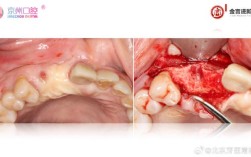

正畸(Orthodontics)与引导组织再生术(GuidedTissueRegeneration,GTR)是两种重要的口腔治疗技术,它们在解决牙齿排列不齐和牙周组织缺损问题时各有侧重,但在特定复杂病例中,它们可以协同作用,实现更佳的...

“种植牙膜钉”这个术语在种植牙领域通常指的是引导骨再生手术中用于固定生物膜的微型钉子,它不是种植体本身,而是辅助材料,以下是关于种植牙膜钉的详细解释:它是什么?目的:在种植牙手术中,尤其是需要进行引导骨再生技术时,使用,作用:将引导骨再...